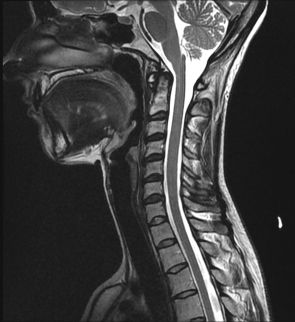

A previously fit and fine man rendered dis-abled in a short 6 weeks. He suffers from diabetes and hypertension so had ended up with the cardiologist, Dr Achilihu. The good cardio man evaluated him in depth and cleared his heart, of course. He also requested for an MRI scan of his neck. This is the gold standard in evaluating a patient with weakness of all 4 limbs.

The MRI scan revealed an obstruction in the neck in my chap. The bones in the neck had worn away the shock absorber and this was now causing pressure on the spinal cord. This is the reason for the weakness in the arms and legs. It is also the cause of the numbness which he describes as ‘cold as ice’.